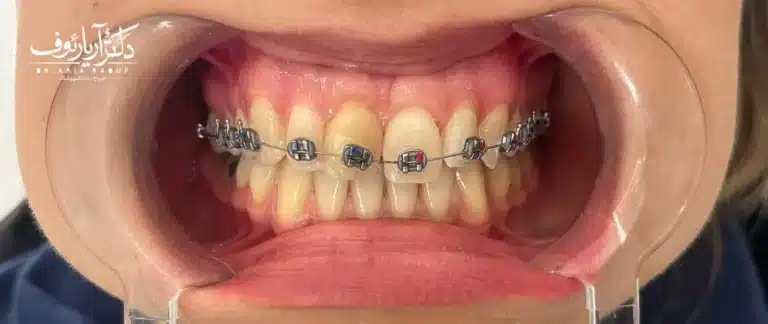

آلبوم تصاویر: حتماً از دکتر بخواهید عکسهای “قبل و بعد” کیسهای مشابه شما را نشان دهد. به جزئیات دقت کنید: آیا خط لبخند هماهنگ است؟ آیا دندانها کاملاً جفت شدهاند؟